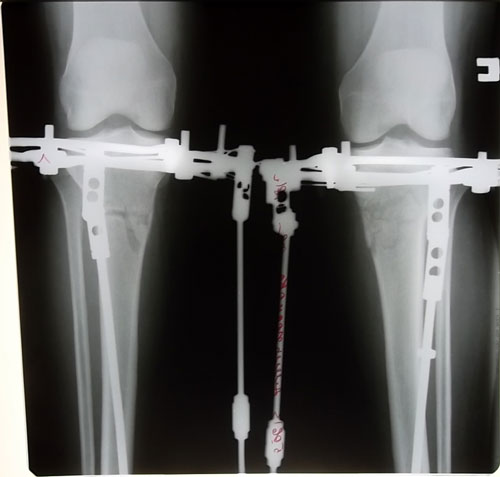

- Диагноз: О-образная деформация ног

- Диагноз: о-образная деформация нижних конечностей